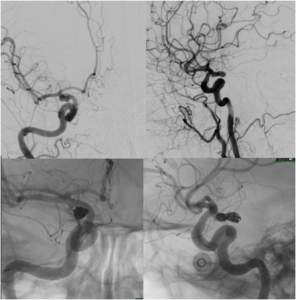

Aneurysm Coiling

Aneurysm coiling refers to the insertion of platinum coils into the aneurysm. A catheter is inserted into a blood vessel and passed using X-ray guidance through the circulation into the brain and then into the aneurysm sac. The microcoils are pushed into the aneurysm through the catheter. Upon depositing within the aneurysm, the coils initiate a thrombotic reaction within the aneurysm. If successful, this prevents further bleeding from the aneurysm.

Balloon Assisted Aneurysm Coiling

Balloon assisted aneurysm coiling is a technique in which a small balloon is inflated within the parent artery of the aneurysm to provide a scaffolding for the coils. This allows for the safe and effective treatment of aneurysm with a broad base (or neck) and with more complex anatomy. a stent may be passed first into the parent artery to serve as a scaffold for the coils.

Stent Assisted Aneurysm Coiling

Stent assisted aneurysm coiling is a technique in which a stent, or tubular piece of mesh, is deposited within the parent artery of the aneurysm to provide a scaffolding for the coils. This allows for the safe and effective treatment of aneurysm with a broad base (or neck) and with more complex anatomy. Placement of an intracranial stent will require administration of anti-platelet drugs, such as aspirin, clopidogrel, or prasugrel.